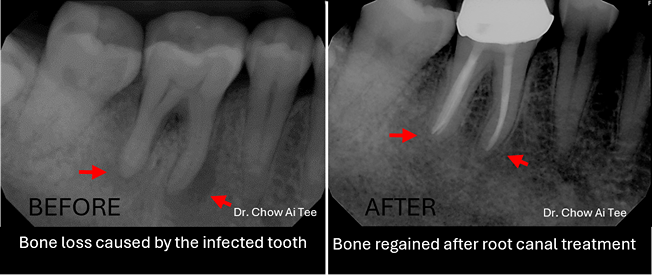

Fortunately, pulling out a tooth is no longer the go-to solution. In most cases, root canal treatment (endodontic therapy) offers a way to preserve the natural tooth. During this procedure, the dentist removes damaged and infected pulp tissue from the tooth, ensuring proper oral function. The first step involves assessing the tooth, identifying the problem, and planning the treatment. Dental X-rays and other diagnostic tools help determine the extent of damage.

A thorough review at one year is essential to ensure that the treatment has been successful, checks for any signs of infection or complications, and confirms that the tooth is healing properly.